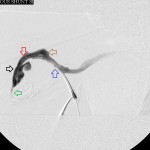

- Right brachial venogram before intervention: green arrow is 1st and juxta-anastomotic stenosis; black arrow is proximal aneurysm; red arrow is 2nd and mid stenosis; brown arrow is 2nd aneurysm; blue arrow is 3rd and distal stenosis.

Clinical problem: Failed right brachiobrachial fistula.

Angiographic findings:

- A high-grade juxta-anastomotic venous stenosis.

- 2 upstream venous aneurysms between which is sandwiched a 2nd high-grade venous stenosis.

- A 3rd venous stenosis, also high-grade, distal to the distal aneurysm.

- Venous collaterals around the right axillary vein due to chronic total occlusion of the right subclavian vein.